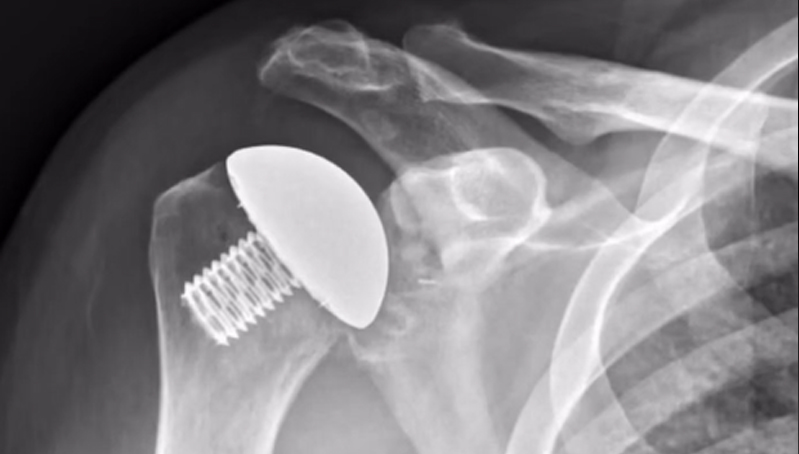

Following a total shoulder arthroplasty

The patient is placed in a sling for about 4 weeks. Their first follow-up appointment takes...

After a total Shoulder Surgery, A LOT goes into surgery!

After a total shoulder is planned we head to the OR.

Two types of total

shoulder replacements:

Anatomic and Reverse. The shoulder is a ball and socket joint. The ball portion